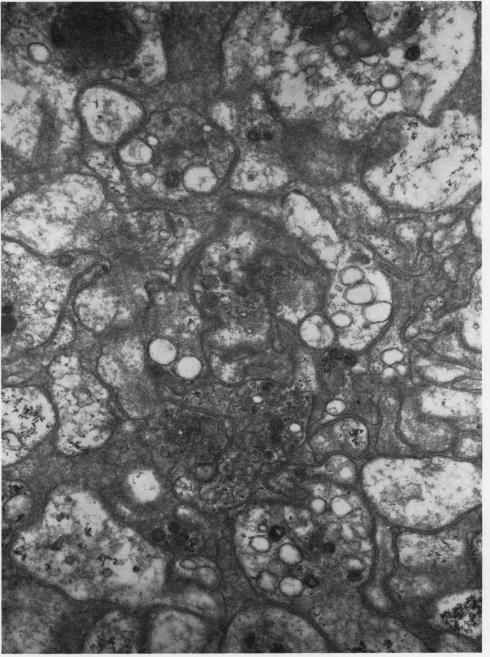

The platelets of a patient with reticulum-cell sarcoma were found to exhibit agglutination and cytopathic changes when her blood was treated with EDTA but not with other anticoagulants. Investigation showed that the phenomenon was caused by a serum factor that was probably an antibody.

当用乙二胺四乙酸(EDTA)处理一名网状细胞肉瘤患者的血液时,发现其血小板出现凝集和细胞病变改变,而用其他抗凝剂处理时则未出现这种情况。研究表明,该现象是由一种可能为抗体的血清因子引起的。